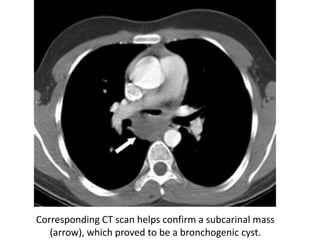

Corresponding CT scan helps confirm a subcarinal mass

(arrow), which proved to be a bronchogenic cyst.

Posteroanterior chest radiographdemonstrates a subcarinal abnormality with increased opacity (*), splaying of the carina, and abnormal convexity of the upper and middle thirds of the azygoesophageal line (arrowheads)

Corresponding CT scanhelps confirm a subcarinal mass (arrow), which proved to be a bronchogenic cyst.